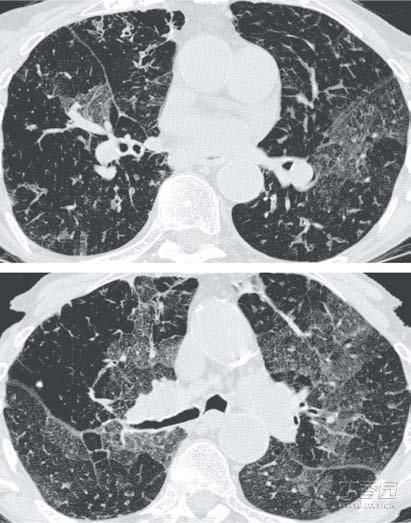

闭塞性支气管炎。

闭塞性支气管炎是一种罕见、致命且不可逆的阻塞性肺病,若患上了这种疾病,别说抽烟了,可能很长一段时间都要在抽血中度过了。